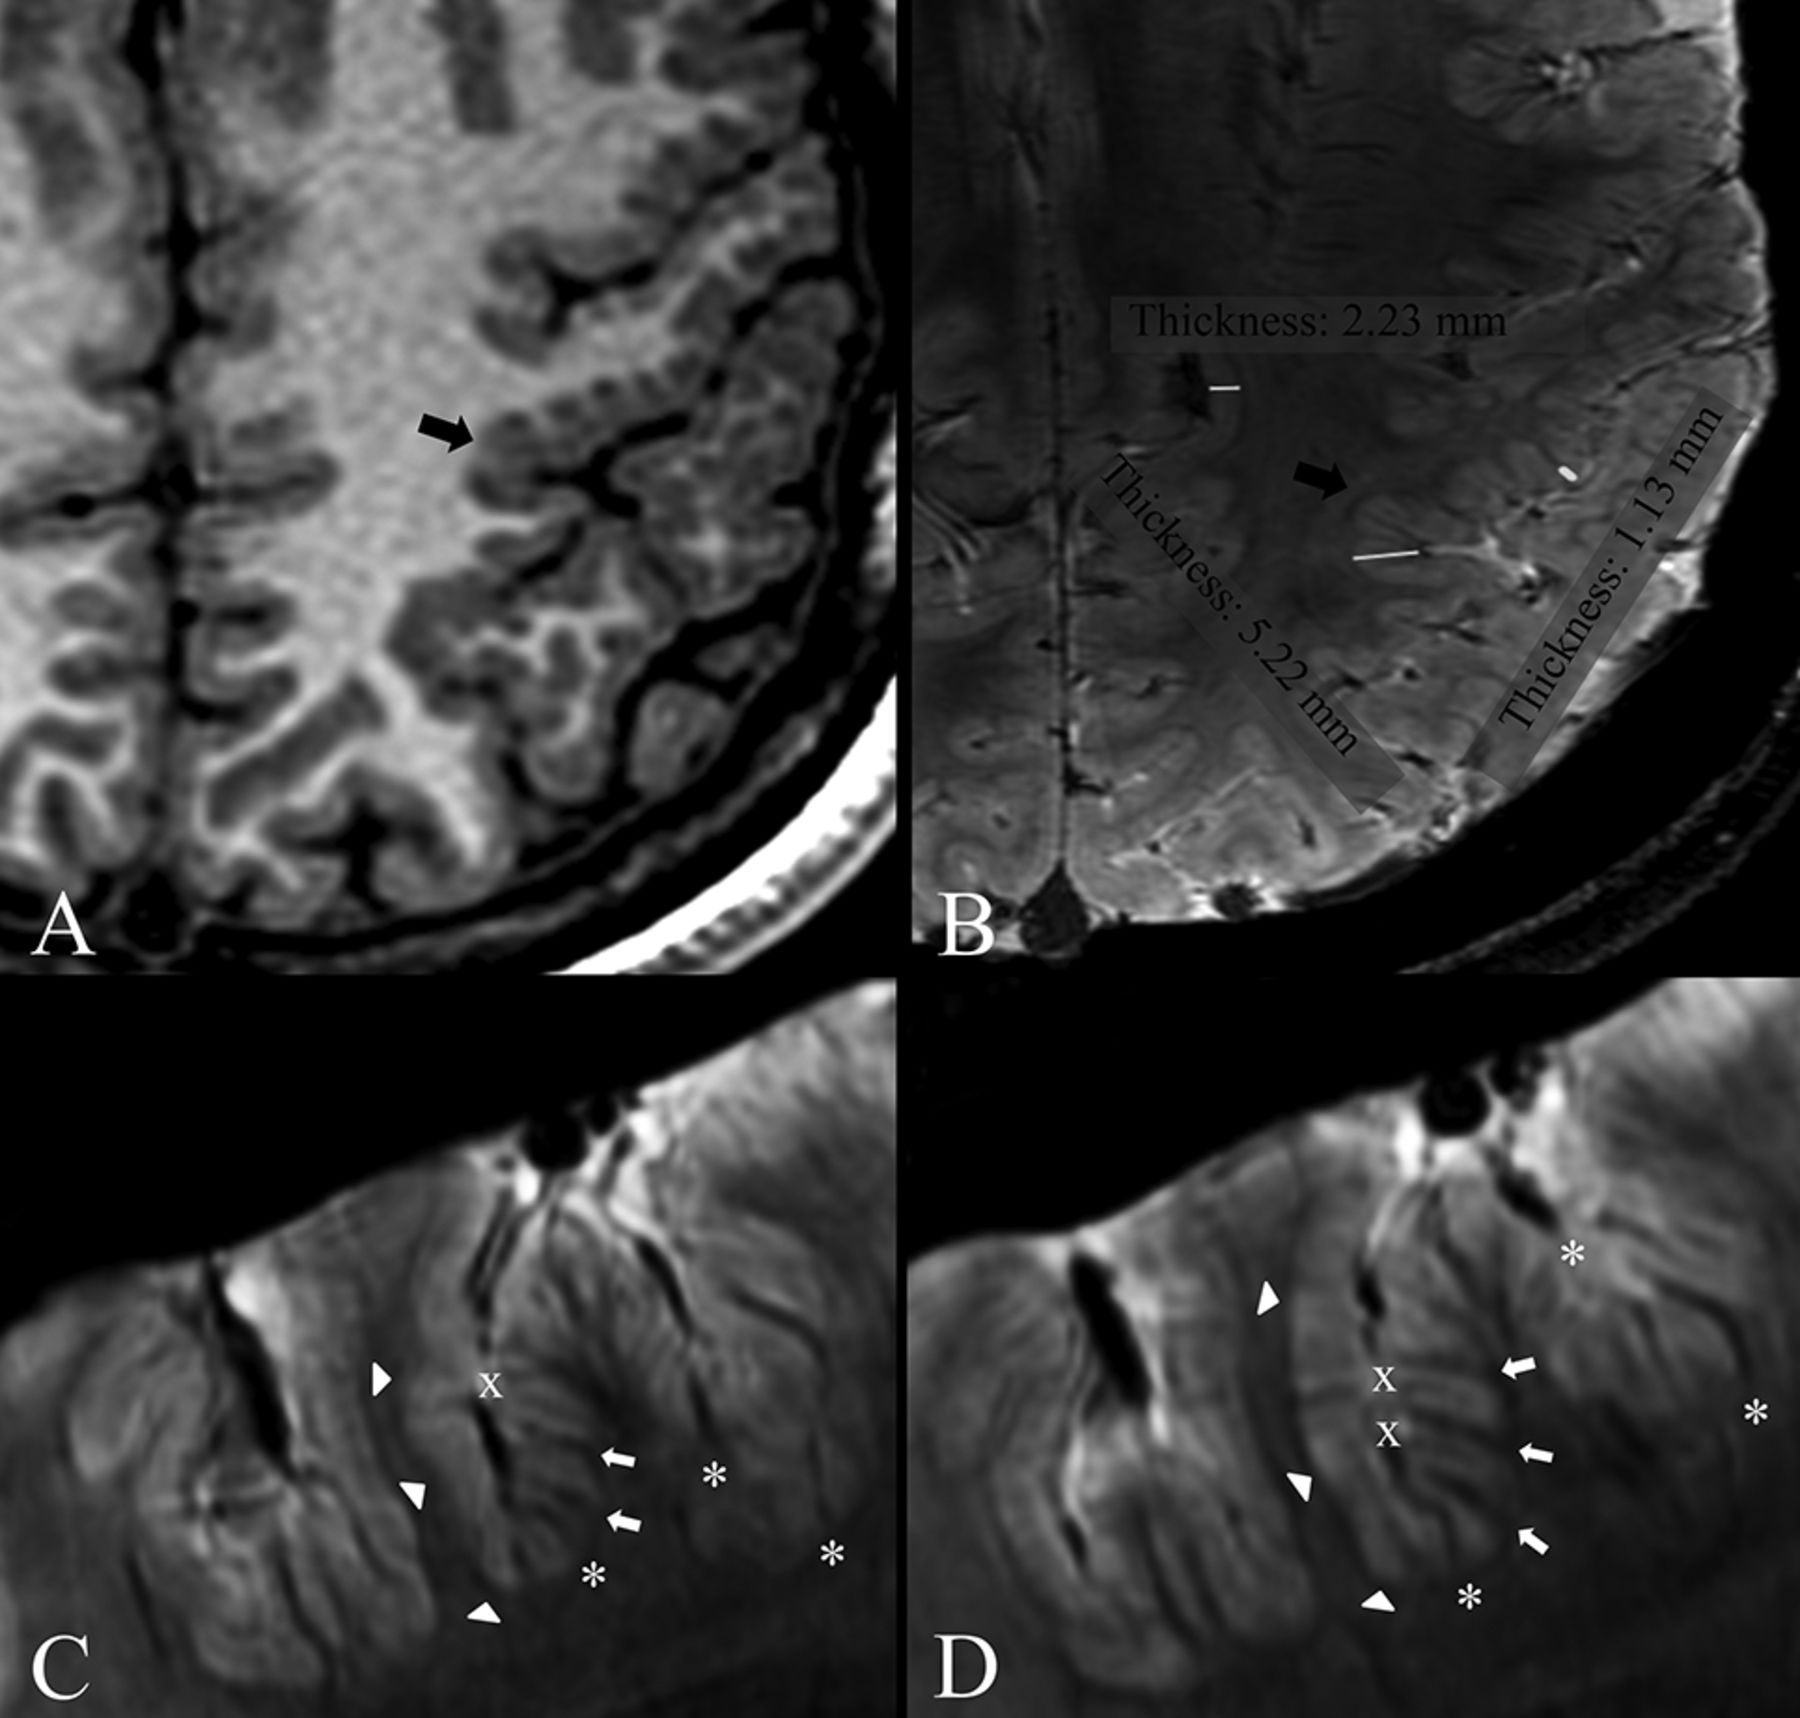

At 3T, we observed perisylvian polymicrogyria that was unilateral in 7 patients and bilateral in 2. Of the 7 patients with unilateral polymicrogyria, 6 had multilobar involvement, and in 1, only a portion of the Sylvian fissure was involved (Fig 1). One patient had diffuse polymicrogyria.

Patient 8. 3T axial (A) and sagittal (B–E) 3D FSPGR, 7T 3D SWAN (F), and magnified images (G, G+1, H), 7T axial 2D TBE FSE-IR (I) and magnified images (L and M). A, Mild cortical thickening in the right frontal operculum. Contiguous sagittal sections across the frontal operculum and the Sylvian fissure on the right (B and D) and left (C and E) sides provide a better comparative view of the morphologic characteristics of malformed-versus-normal cortex. B, An abnormal right Sylvian fissure (arrow), which is vertically oriented, shortened, and bordered by thick and irregular cortex. D, Thickening of the cortex in the inferior frontal gyrus and superior temporal gyrus (arrows). F, Two contiguous expanded views, from caudal (G) to rostral (G+1), provide ultra-high-resolution details of the right frontal operculum, which are not visible at 3T (A–E), substantiating the presence of a polymicrogyric cortex. H, A magnification of the homologous contralateral region clearly enhances the appreciation of the difference in folding of the polymicrogyric and normal cortex. I, Magnifications (L and M) show a hypointense line representing the gray-white matter interface and provide a high definition of the polymicrogyric (L, arrows) and normal (M) cortex, making it easier to appreciate irregularities in thickness and folding of the polymicrogyric cortex.

7T provided additional details to 3T findings and revealed more extensive areas of polymicrogyria in all patients. In particular, in 3 patients (patients 4, 7, and 8) in whom 3T FSPGR imaging had revealed unilateral polymicrogyria, 7T SWAN imaging confirmed a unilateral distribution but detected more extensive involvement (Fig 1). In 3 patients with bilateral polymicrogyria at 3T (patients 1, 3, and 9), 7T SWAN revealed more extensive involvement. Four patients (patients 2, 5, 6, and 10) who had been classified as having unilateral polymicrogyria at 3T exhibited bilateral involvement at 7T (On-line Fig 2). In patient 2, 3T FSPGR showed left posterior polymicrogyria engaging the left temporoinsuloparietal region and the medium and superior occipital gyri. 7T SWAN imaging disclosed that polymicrogyria also involved the right posterior insula. In patient 5, in whom 3T FSPGR showed left frontotemporoparietal polymicrogyria along the whole Sylvian fissure, 7T SWAN revealed polymicrogyria also in the right frontal operculum. In patients 6 and 10, the polymicrogyric cortex had right temporoparietal distribution at 3T FSPGR, while 7T disclosed abnormal infolding and thickening of the left frontal operculum. In patient 10, 7T SWAN also showed that polymicrogyria involved the area around the whole left Sylvian fissure, left anterior insula, and left anterior temporal region.

In all patients, TBE imaging revealed a hypointense line corresponding to the gray-white matter interface, providing a high definition of the borders of the polymicrogyric cortex (On-line Figs 3 and 4). TBE imaging substantiated SWAN findings and, providing a precise topographic definition of the gray-white matter junction, made the examiner more confident about the extent of polymicrogyria, especially when the border between gray and white matter was poorly defined or the polymicrogyric cortex merged with a seemingly normal cortex (On-line Figs 3 and 4).